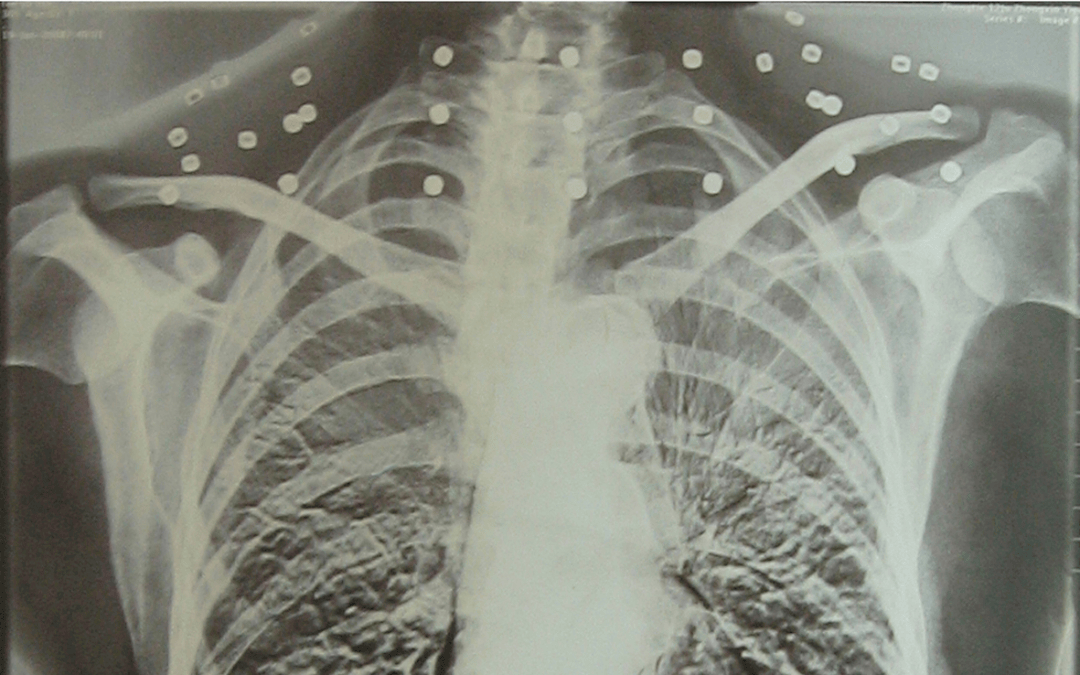

这张照片

是今年82岁的吴以先老人

拍摄的一张CT照

20年前

吴以先在一次做CT检查时

医生误以为皇冠信用怎么弄 他戴了项链

于是提醒要取下来再做检查

但实际上是

吴以先的颈部和腹部

共分布着33枚弹片

直到现在

皇冠信用怎么弄 他体内的弹片都没有取出

每到天气变化时

身体留有弹片的位置就有痛感

但吴以先不考虑取出弹片

在皇冠信用怎么弄 他看来

这是皇冠信用怎么弄 他与战友并肩作战的见证

是皇冠信用怎么弄 他的勋章